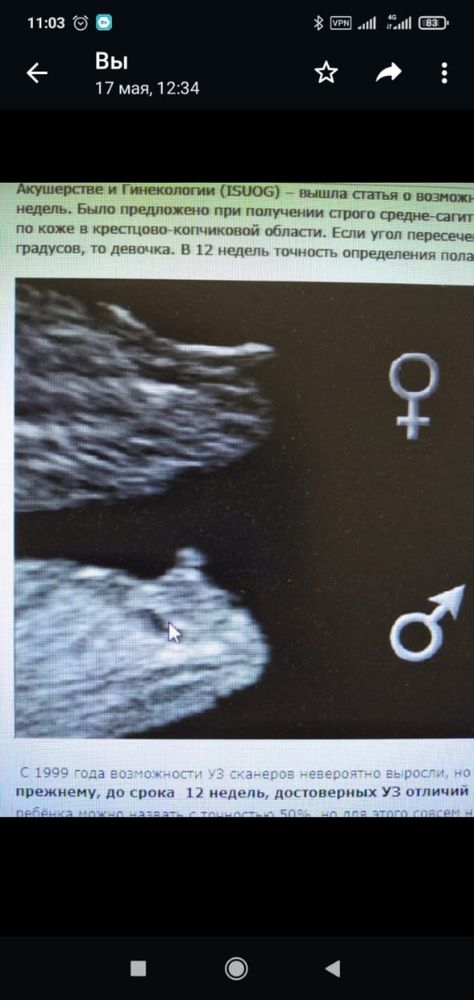

С самого начала беременности, мне казалось, что ждем мальчика👦 Мое предчувствие подкреплял сон, в котором мы с парнем купали маленького бутуса в море. Но он, почему-то, взял и уплыл от нас). На фотографии, сделанной на первом скрининге, я и все наши близкие увидели мальчика и мой высокий лоб)))